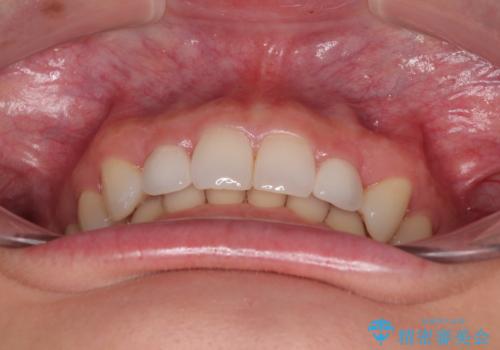

前歯のデコボコと小さい歯を改善 インビザラインとオールセラミッククラウン

矮小歯の前後にスペースを作るようにインビザライン矯正治療を計画し、矯正治療後にオールセラミッククラウンによる補綴治療を行うこととしました。

何とか矮小歯を改善するスペースを作ることはできましたが、過蓋咬合を改善するには至りませんでした。